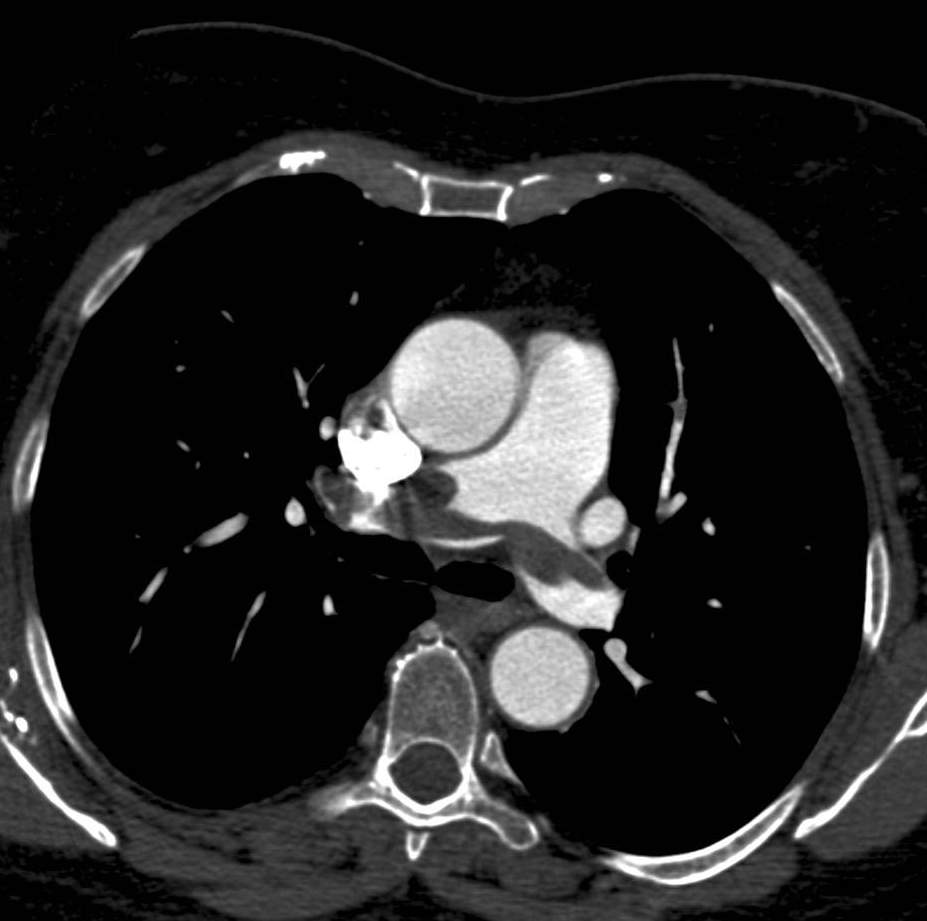

8.1.8. Cardiac tumors

The most common primary cardiac tumor is the myxoma which can originate from the endocardium or the valves. They typically appear as mobile, intra-cavital masses (on echocardiography, CT or MRI). The most common tumor originating from the myocardium is rhabdomyoma, often appearing multifocally. Secondary tumors of the heart can be metastases from true hematogenous spreading; the primary tumors in these cases are most often breast-, lung carcinomas or melanoma but tumors can also spread directly from nearby thoracic tissues, through direct propagation, most commonly from pulmonary tumors. Echocardiography can suspect tumorous infiltration of the cardiac wall or chamber; however, it is unable to show integrally the possible extra-cardiac tumor component and cannot differentiate securely tumorous lesions from the normal myocardium. Another fundamental question that need to be answered is how much of the actual intra-cavital pathologic lesion is made up of viable tumor tissue and how much of it is a thrombotic growth on its surface. This is best assessable with MRI examination. Tumors with extra-cardiac, mediastinal or pulmonary infiltration might require the use of CT examination in order to determine the full extent of the tumor components.